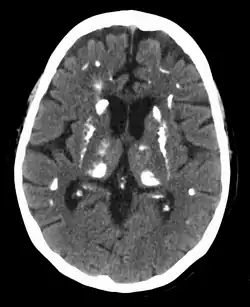

Hyperparathyroidism

Hyperparathyroidism is an increase in parathyroid hormone (PTH) levels in the blood.[1][4] This occurs from a disorder either within the parathyroid glands (primary hyperparathyroidism) or as response to external stimuli (secondary hyperparathyroidism).[1] Symptoms of hyperparathyroidism are caused by inappropriately elevated blood calcium excreted from the bones into the blood stream in response to increased production of parathyroid hormone.[1] In healthy people, when blood calcium levels are high, parathyroid hormone levels should be low. With long-standing hyperparathyroidism, the most common symptom is kidney stones.[1] Other symptoms may include bone pain, weakness, depression, confusion, and increased urination.[1][2] Both primary and secondary may result in osteoporosis (weakening of the bones).[2][3]

In 80% of cases, primary hyperparathyroidism is due to a single benign tumor known as a parathyroid adenoma.[1][2] Most of the remainder are due to several of these adenomas.[1][2] Very rarely it may be due to parathyroid cancer.[2] Secondary hyperparathyroidism typically occurs due to vitamin D deficiency, chronic kidney disease, or other causes of low blood calcium.[1] The diagnosis of primary hyperparathyroidism is made by finding elevated calcium and PTH in the blood.[2]